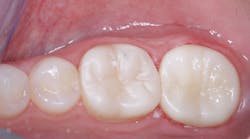

Color of zirconia crowns

Obtaining optimum color for zirconia crowns has been a near impossibility (figure 4). Almost all zirconia crowns come back to you a shade or two too light. If you require low-cost zirconia crowns from your lab, you have only one choice—have the crowns made one or two shades darker than the shade guide color you selected. If you want 3Y class 5 (the original formulation) zirconia crowns that actually have the correct color, you will pay significantly more (figure 5).

The 3Y zirconia can be internally stained at the presintered stage to achieve the color you desire after sintering.

New formulations of zirconia are coming on the market rapidly; for these, companies are not using the original zirconia formulation. Some of the crowns look more esthetically pleasing than the original zirconia formulation, but they have lower strength and need long-term research to validate their formulations.